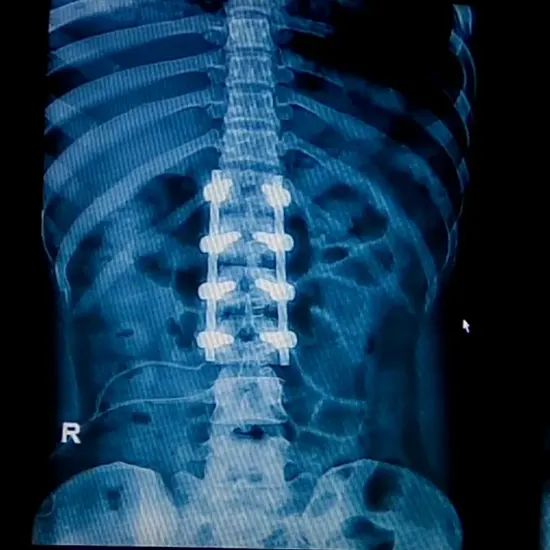

What is an X-ray LS Spine AP Lateral View Test? An LS spine (lumbosacral spine) X-ray is a safe and painless way to see the lower back area made up of five lumbar vertebrae (L1 to L5) and the sacrum (a triangular bone at the end of the spine).

• To examine for anomalies in the spine's curvature, such as lordosis, kyphosis, scoliosis, or birth deformities.